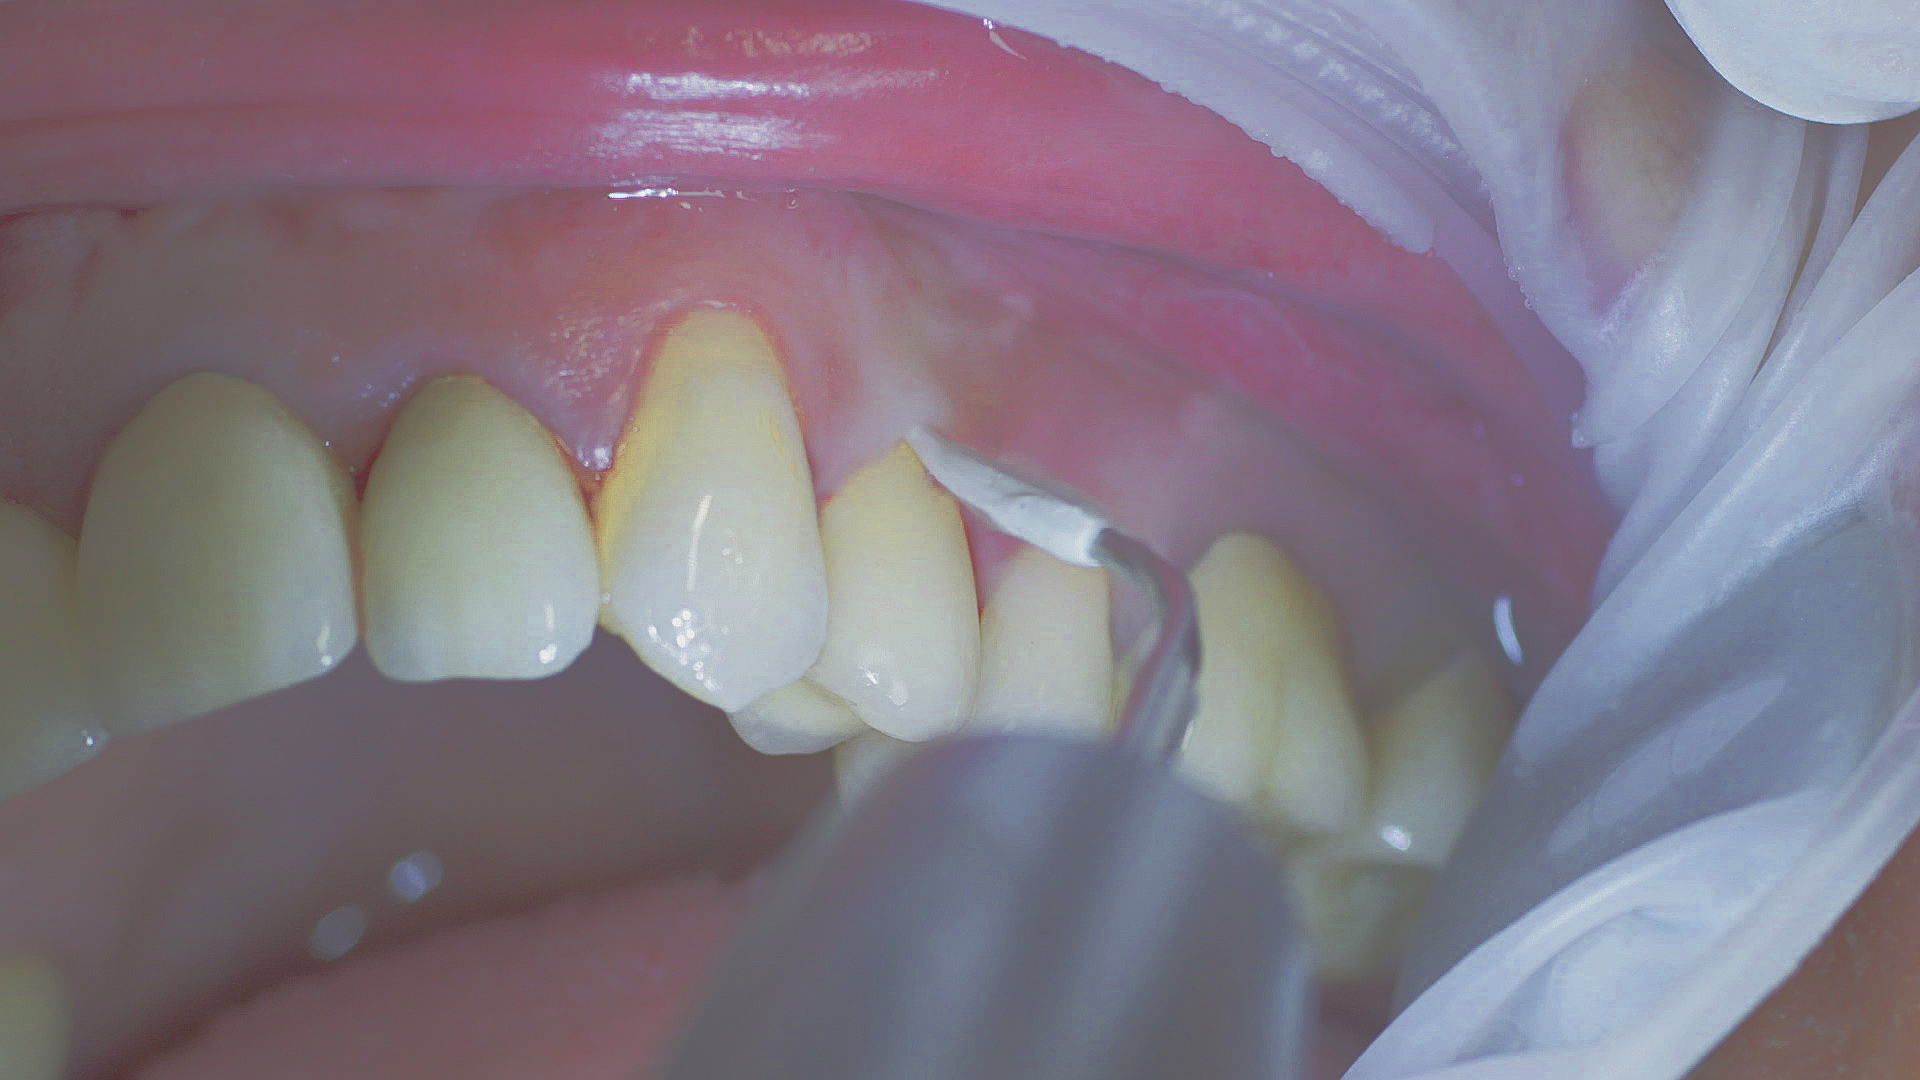

Every dental examination is based on a detailed medical history combined with targeted diagnostics con- taining as much detail as possible: The dentist records systemic risk factors such as diabetes or smoking and identifies any potential increased tendency to inflammation.[3] Hard and soft tissues are examined and periodontal pockets are probed in a screening test according to PSR (Periodontal Screening and Recording). In case of abnormal findings, the periodontal status is then re- corded and therapy is initiated where necessary. This treatment begins with professional biofilm management, by using, for example, rotary cups and polishing com pounds (Fig. 1), and comprehensive instructions in oral hygiene. Sonic or ultrasonic systems remain an effective alternative or supplement to manual instruments for sub- gingival debridement and biofilm management (presentation by Prof. Dr Ulrich Schlagenhauf; Fig. 2). Supplementary use of photodynamic therapy, air polishing or local and systemic antibiotics is not adequately documented (Prof. Dr Sema Hakki).[4] According to Dr Sergio Bizzarro, improved biomarker diagnostics may lead to an increase in customised patient therapy in the future.